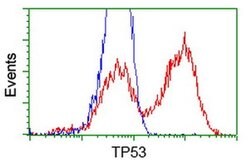

| Applications | Flow Cytometry, Immunocytochemistry, Immunofluorescence, Western Blot |